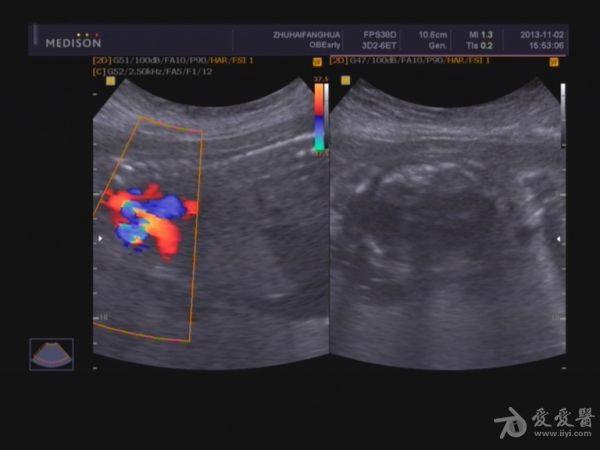

胎盘:附着于子宫后壁,厚度44mm,成熟度:0级,范围面积大,几乎覆着全后壁。

脐带:结构正常,脐动脉血流参数:SPV:33cm/s,PI:1.0,RI:0.62,S/D:2.6。典型图片如下:

2.胎儿畸形,胸、腹腔大量积液,

3.超大胎盘,羊水少。